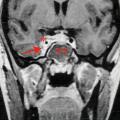

Plus rarement, il peut s’agir d’une thrombose du sinus caverneux (fig. 4) – notamment sur cellulite de la face, avec œdèmes palpébraux, céphalées et fièvre.